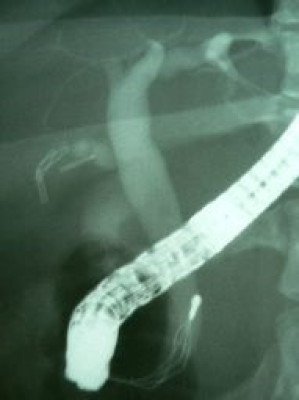

Coledocolitiasis con antecedente de colecistectomía por laparoscopía

Envíado por Dr. Carlos Miguel Zavaleta Consuegra